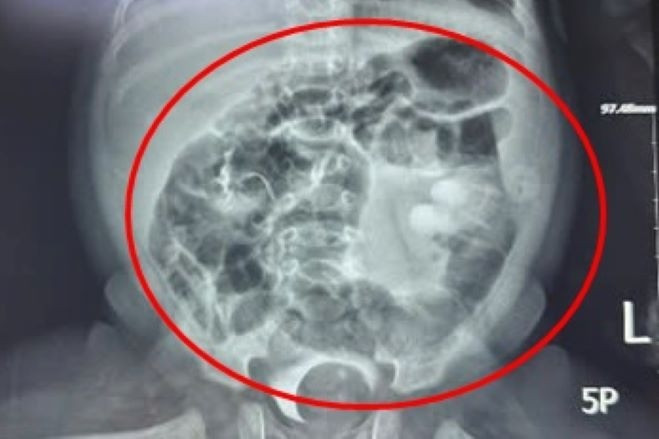

Bé trai 1 tháng tuổi có khối khổng lồ chiếm gần trọn lòng bàng quang